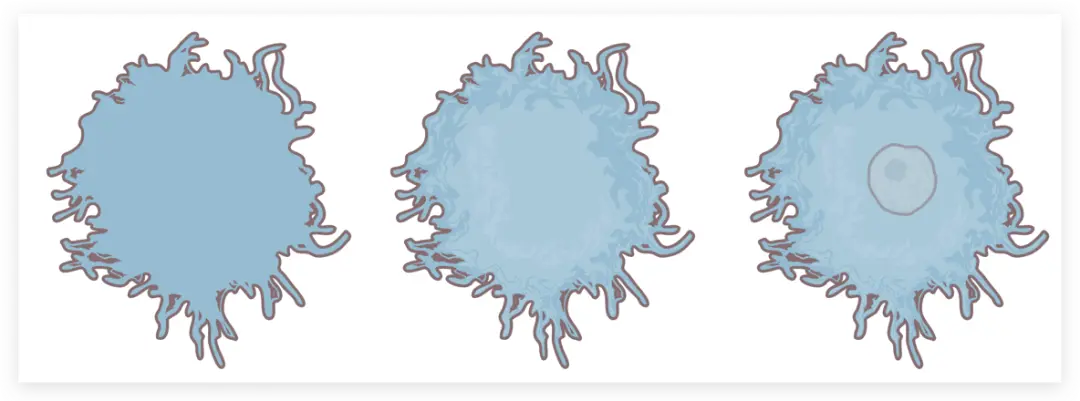

然后来画最中间这部分粉色细胞

同样使用钢笔工具勾线加填色

钢笔工具中间浅白色部分

四周这些细碎的浅白色色块也不要遗漏

接着细胞核

钢笔工具一点点勾勒出里面的轮廓

最上面加个色块

最上面还有两层浅色色块不要漏掉

接着来画中间肿瘤细胞部分

虽然形状不同但方法一致

先用钢笔工具勾勒出外轮廓

再上色

一层层叠加图层至完成